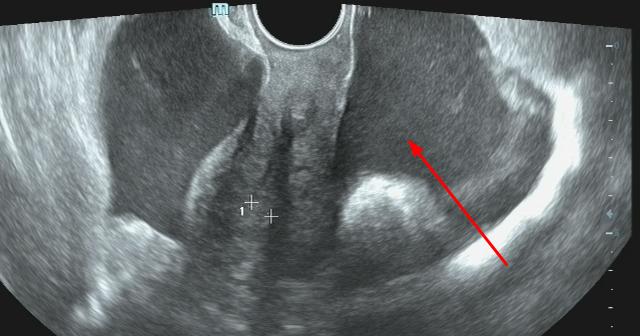

1、生理性的积液

如卵巢排卵后,会形成一些生理性积液,后期一般会自己吸收。

少量